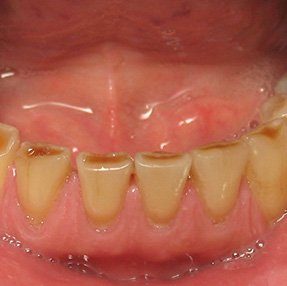

2. Attrition

Attrition represents the physiological wearing of teeth through tooth-to-tooth contact. This natural process accelerates significantly in patients with:

The clinical presentation typically includes flattened occlusal surfaces, matching wear facets on opposing teeth, and potentially reduced vertical dimension in advanced cases.